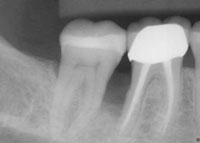

• Periodontitis: Advanced stage affecting supporting bone and tissues

If left untreated, gum disease can lead to damage of the supporting structures of the teeth and may eventually result in tooth loss. Early intervention helps in controlling the condition and maintaining overall oral health.

Why Early Treatment is Important

The treatment approach depends on how advanced the condition is. Early stages can often be managed with non-surgical methods, while more advanced cases may require additional procedures.